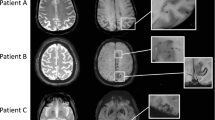

In total, 19 ex vivo MRI-targeted microhemorrhages were available for analysis (nine from the Boston data set and ten from the Utrecht data set). On histopathology, 12 proved to be old, and seven acute microhemorrhages. In seven (three acute and four old) out of 19 microhemorrhages, the presumed involved vessel could be identified on the adjacent Aβ-stained section. In six out of these seven vessels, the walls were negative for Aβ (Fig. 1). Interestingly, in one autopsy case, four additional vessels with fibrinoid necrosis (confirmed by phosphotungstic acid/hematoxylin stain) were observed, for which adjacent Aβ-stained sections were available. None of these vessels were positive for Aβ (Fig. 2).

Vascular Aβ was absent in the walls of six out of seven vessels that were involved in microhemorrhages in cerebral amyloid angiopathy. A recent microhemorrhage was identified on an H&E-stained section, characterized by the presence of intact erythrocytes (arrows) in the parenchyma, surrounding a penetrating cortical vessel (a, inset shows enlargement of boxed area; adapted from [22] with permission). The adjacent Aβ-stained section revealed that the involved vessel was negative for Aβ (broken arrows), whereas neighboring vessels did contain Aβ (arrows) (b, inset shows enlargement of boxed area, broken arrows indicate absence of Aβ in the wall of this vessel). In another case, an old microhemorrhage was identified on an H&E-stained section, characterized by the focal deposition of hemosiderin (blue deposits in inset) in the parenchyma, surrounding a cortical vessel (broken arrow in inset) (c, inset shows Perl’s Prussian blue staining of the area outlined in the box for enhanced detection of hemosiderin). The adjacent Aβ-stained section revealed that the involved vessel was negative for Aβ (broken arrows in inset), as well as vessels in close proximity to the microhemorrhage (broken arrows), whereas vessels further away did contain Aβ (arrows) (d, inset shows enlargement of boxed area). All scale bars indicate 250 µm